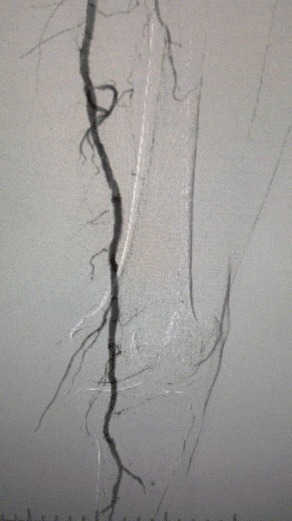

·Preoperative Imaging: Severe, diffuse calcified stenosis in bilateral lower limb arteries

Given the complex vascular condition, we selected the ThorCrack Peripheral IVL Balloon Dilatation Catheter System. Due to the patient’s limited tolerance, staged interventional procedures on both lower limbs were performed.